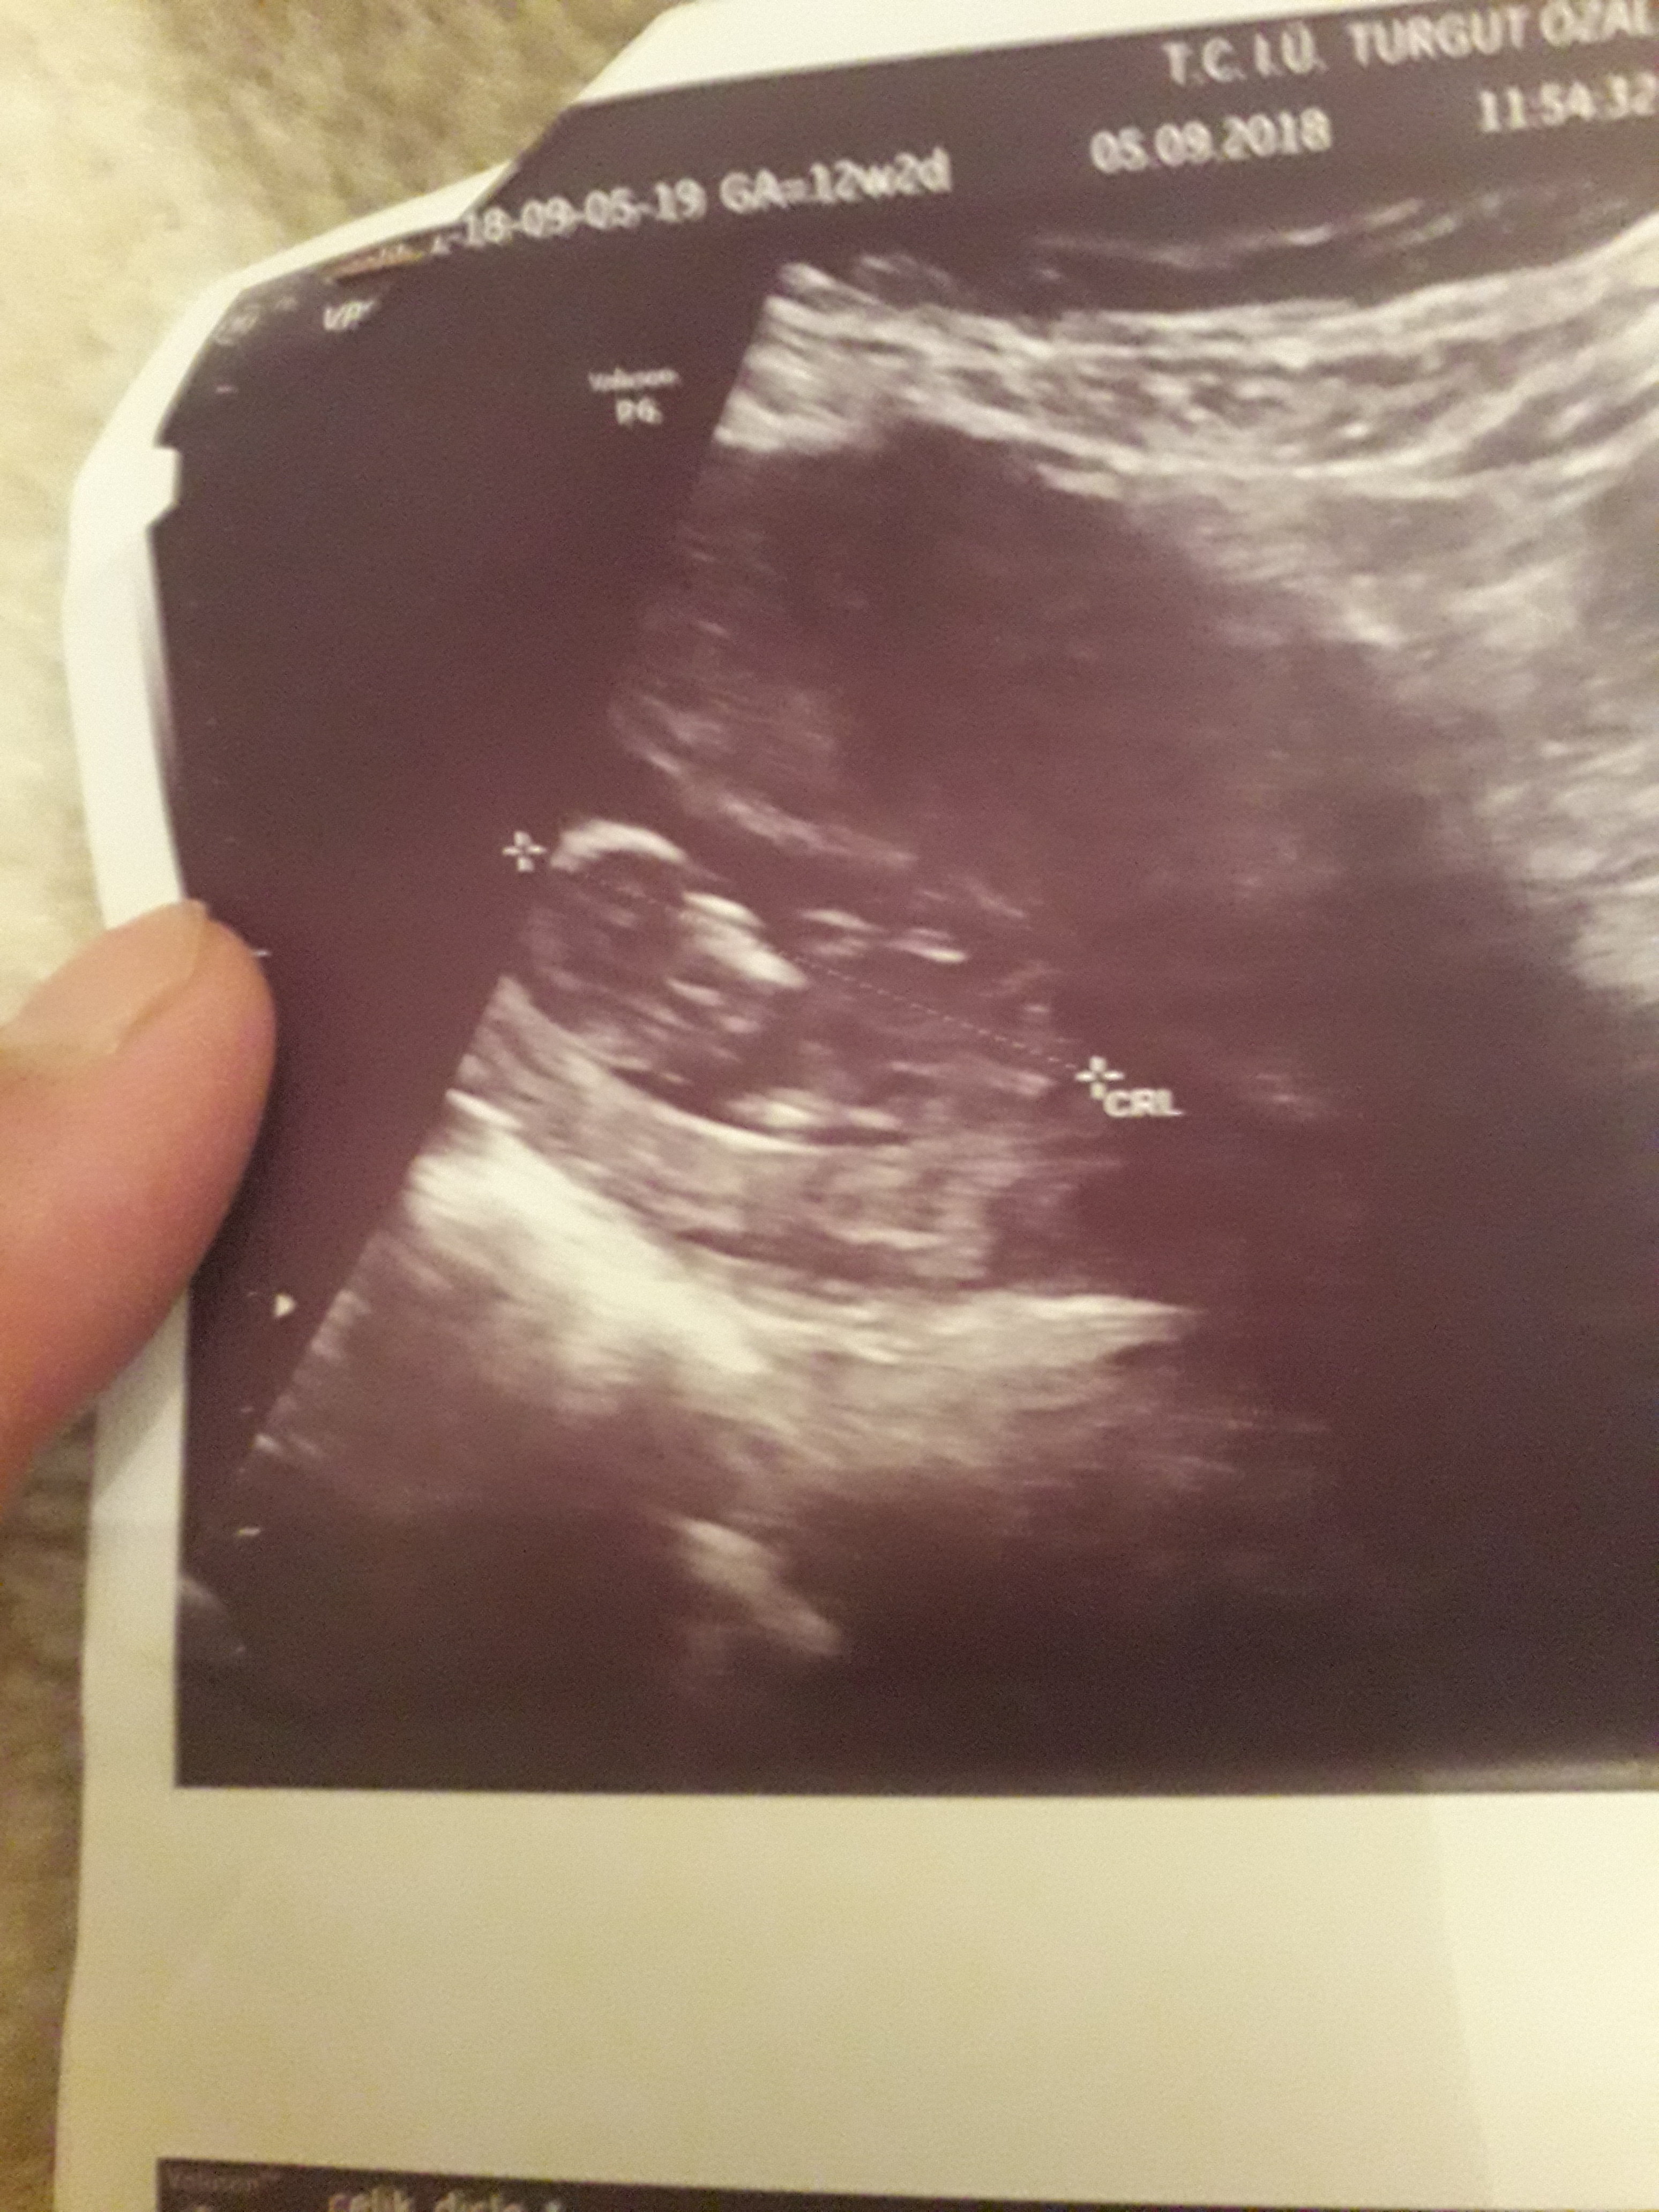

Dun malatyada verildi 12 +4 gunluk lutfen yorumlayin

nub çıkıntısının üzerinde imleç var cinsiyet anlaşılmıyor ilk sayfayı incelemenizi öneriyorum görselin kalitesi konu içinde yer alan görselle aynı olmalıdır.

Görsellerde nub çıkıntısı belli değil . Ultrasonu yapan doktor cinsiyeti hakkında bilgi vermiştir mutlaka ama şunu belirtmeden geçmeyeyim. Bu haftalarda cinsiyet tahmininde yanılma payı çok yüksek 17-19 ve 20 ci haftalarda bebeğin cinsiyetini net olarak öğrenebilirsiniz.